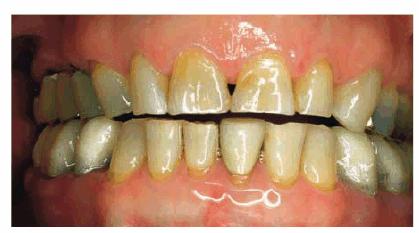

Goldstein cited the revolutionary concept that esthetic dentistry is, in fact, a health service.6 During the last decade, older adults who elected to have treatments that involved all esthetic disciplines embraced this concept of oral health. A good example of an older adult undergoing extensive esthetic dental treatment appears in Figures 29-1A to C 29-1D to F 29-1G 29-1H 29-1I and J 29-1K 29-1L 29-1M 29-1N, and 29-1O

Figure 29-1A to C: This 76-year-old lady presented for treatment after a lifetime of dissatisfaction with her crowded teeth.

Figure 29-1D to F: Tooth-colored brackets were applied because their esthetic appearance gave the patient the confidence to smile during treatment.

Figure 29-1G: After the removal of the orthodontic appliances, the teeth are much straighter but still discolored.

Figure 29-1H: After restorative treatment featuring tooth- colored restorations and bleaching, the patient has the smile she has always wanted.

Figure 29-1I and J: Note that the formally eroded cervical areas have better contour and will deflect food particles better.

Figure 29-1K: Note the crowding of the mandibular anterior teeth.

Figure 29-1L: The teeth are less crowded, and the new tooth-colored restorations have been placed.

Figure 29-1M: The maxillary arch shows anterior crowding and defective amalgam restorations.

Figure 29-1N: Following 12 months of orthodontic treatment, the patient's amalgam restorations were replaced with posterior composite resin.

Figure 29-1O: Interdisciplinary 949o141j therapy including orthodontics, periodontics, and restorative dentistry combined to produce this attractive result 2 years following the initiation of treatment in this now younger-looking 78-year-old lady.